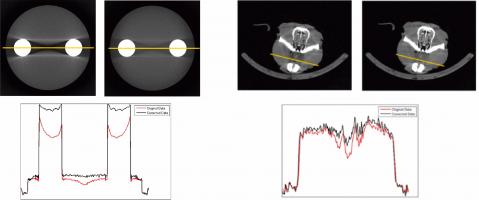

Scattered photons highly degrade the quality of X-ray images and their effect has become more important due to the increasing interest in cone-beam geometry for the acquisition of CT (CBCT) and micro-CT data. The random nature of scatter events and the great influence of the sample suggest that the most accurate methods for their estimation are Monte Carlo (MC) techniques, but their use is usually hampered by the large computation time required to obtain an acceptable estimation of the scattered radiation. We present an approach for scatter correction in CBCT by MC estimation, speeding up the computation by means of general purpose graphic processing units (GPGPU) and developing a framework for the automatic correction and reconstruction of projection data.